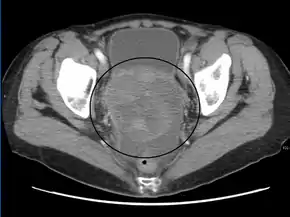

CT scanning is preferred to assess the extent of the tumor in the abdominopelvic cavity, though magnetic resonance imaging can also be used.[19] CT scanning can also be useful for finding omental caking or differentiating fluid from solid tumor in the abdomen, especially in low malignant potential tumors. However, it may not detect smaller tumors. Sometimes, a chest x-ray is used to detect metastases in the chest or pleural effusion. Another test for metastatic disease, though it is infrequently used, is a barium enema, which can show if the rectosigmoid colon is involved in the disease. Positron emission tomography, bone scans, and paracentesis are of limited use; in fact, paracentesis can cause metastases to form at the needle insertion site and may not provide useful results.[20] However, paracentesis can be used in cases where there is no pelvic mass and ascites is still present.[20] A physician suspecting ovarian cancer may also perform mammography or an endometrial biopsy (in the case of abnormal bleeding) to assess the possibility of breast malignancies and endometrial malignancy, respectively. Vaginal ultrasonography is often the first-line imaging study performed when an adnexal mass is found. Several characteristics of an adnexal mass indicate ovarian malignancy; they usually are solid, irregular, multilocular, and/or large; and they typically have papillary features, central vessels, and/or irregular internal septations.[22] However, SCST has no definitive characteristics on radiographic study.[23]